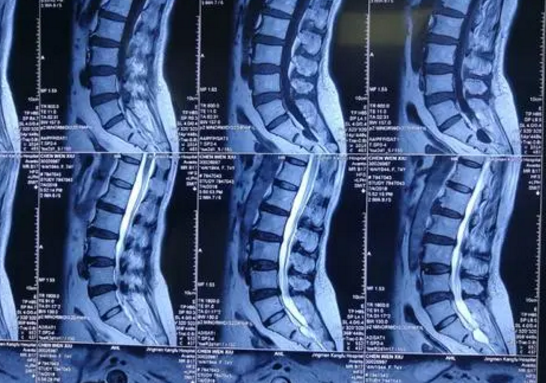

马尾神经属于周围神经的一种,马尾神经损伤导致的马尾综合征是指马尾神经因外界因素受到压迫或损伤,使其发生麻痹、紊乱或功能不全,不能正常的调节支配区域的运动、感觉、痛觉、知觉、温度等功能的调节。如果马尾神经因缺血时间过长或并发继发水肿或麻痹加重是会有截瘫的可能。

马尾综合征的症状其实在临床上是比较常见的,大多是由于各种先天或后天的原因致腰椎管绝对或相对狭窄,压迫马尾神经而产生一系列神经功能障碍。1949年Verbiest首次临床报告且将其命名为马尾神经综合征。